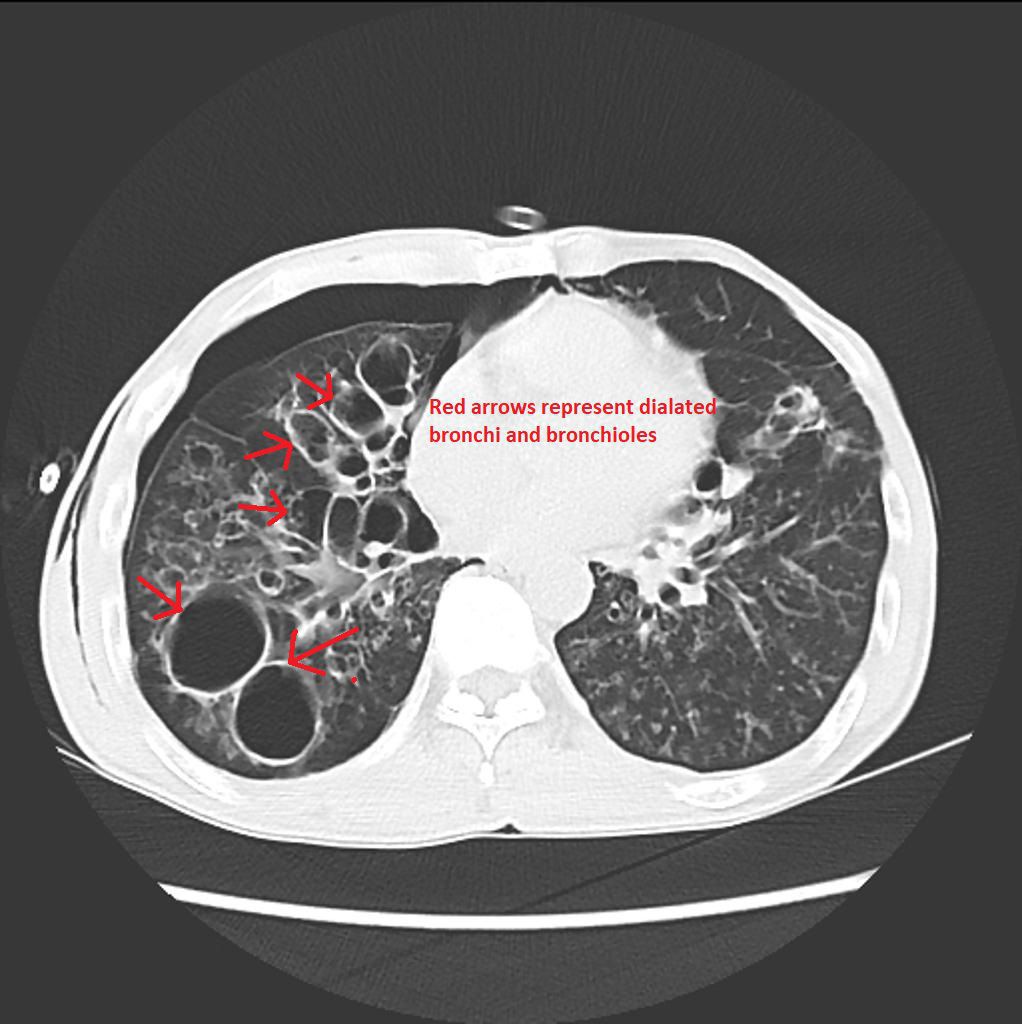

Bronchiectasis refers to the dilatation of the small airways leading to difficulty in breathing. High-resolution CT is typically the diagnostic modality of choice for bronchiectasis. Following findings are usually demonstrated on CT: - diameter of bronchus 1.5 times greater than that of pulmonary artery - failure of bronchial tapering - thickened bronchial walls - loss of lobar volume - cysts with defined borders Reference: https://www.wikidoc.org/index.php/Bronchiectasis_CT Image via: https://www.wikidoc.org/index.php/Bronchiectasis_CT -